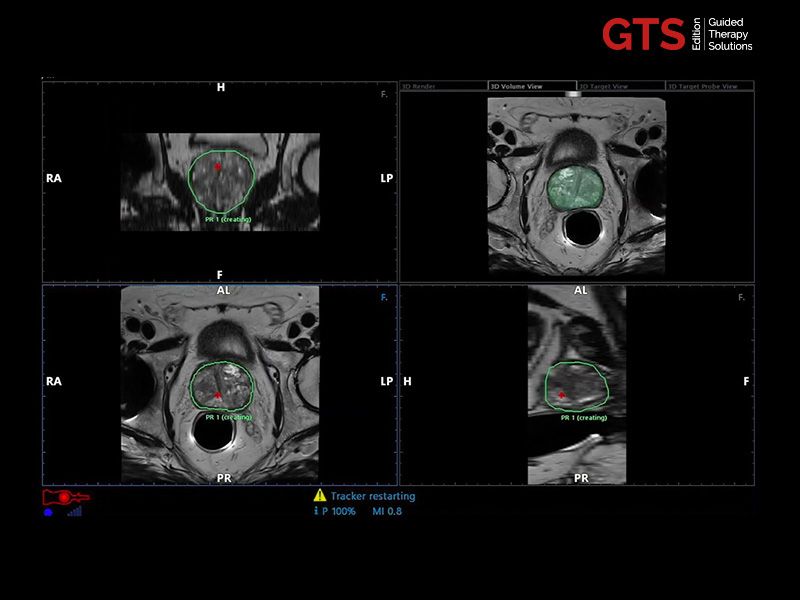

The targeted and systematic biopsy samples will be automatically saved in a 3D prostate rendering volume, a complete and clear report is automatically completed and attached to each procedure.

Transperineal & transrectal targeted biopsy (based on a 3D prostate reconstruction & sample mapping) - UroFusion report - Automatically generated